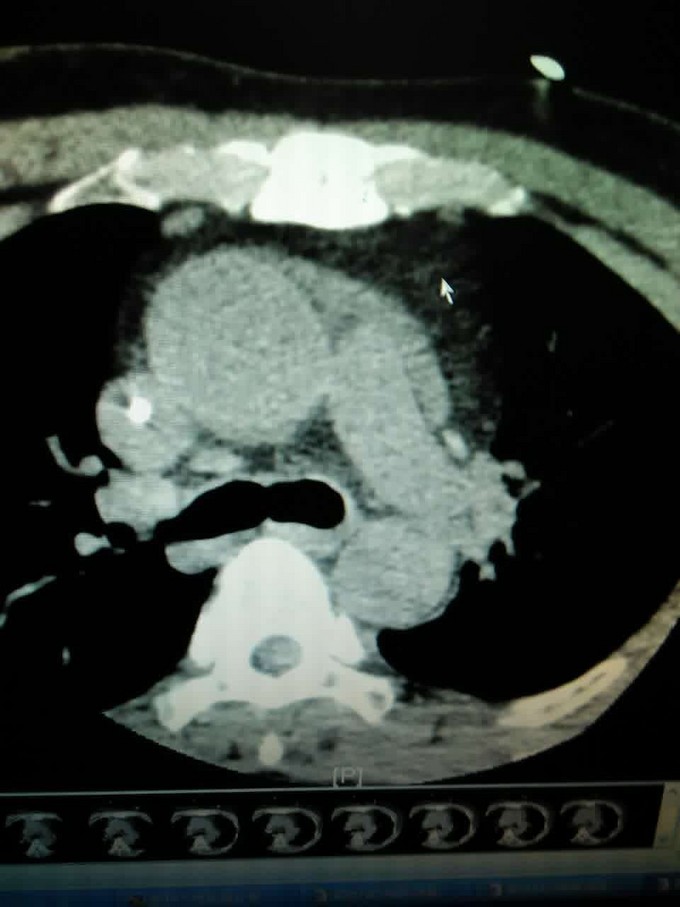

主诉:反复中上腹痛10天 现病史:患者十天前无明显诱因出现中上腹痛,呈持续性钝痛,阵发性加剧,无向腰背部发射,与饮食或体位无明显关系,休息后不可缓解。伴有腹胀、恶心,无呕吐,无反酸,嗳气,没有尿黄,身目黄染,没有发热、畏寒。于当地诊所就诊,诊断为“胃痛”,予药物(具体不详)治疗后疼痛无缓解。遂于罗定市人民医院就诊,住院期间有发热,最高体温不超过39度,小便颜色较前加深,未出现身目黄染。查淀粉酶1700u/L,腹部CT提示:急性胰腺炎并胰周少量渗出,胆囊小结石。诊断为急性胰腺炎,予停留胃管,行ERCP手术未成功,予药物治疗,较前无明显缓解。